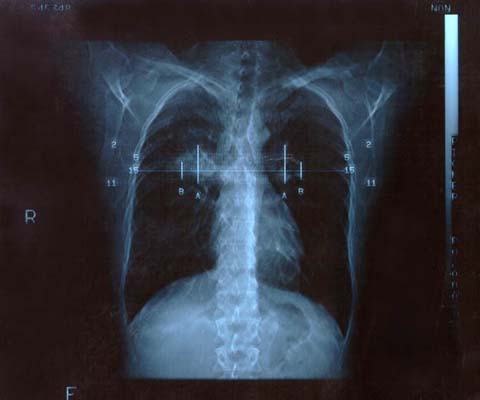

Scan 25th March 1999 No5